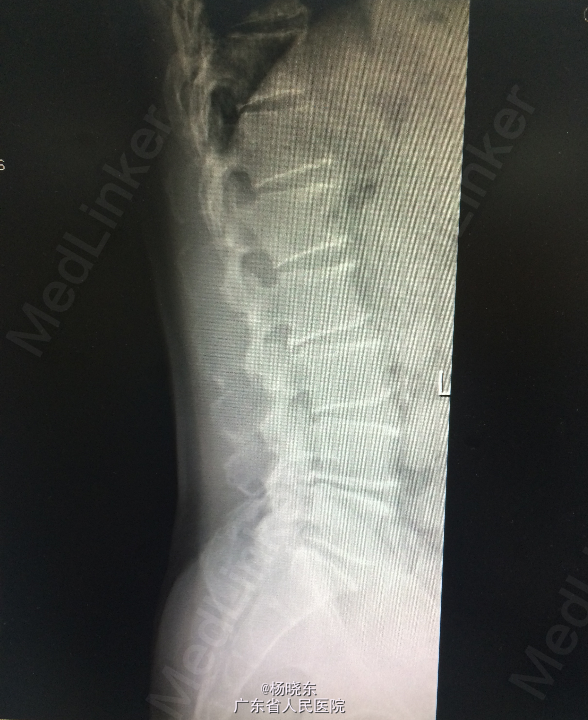

查体:贫血貌,心肺腹查体无特殊。 辅查: 1.全长双下肢长骨正位+尾椎正侧位+肋骨正位+右关节正位+骨盆正位+腰椎正侧位+下胸椎正侧位放射常规照片示:考虑多发性骨髓瘤(多发骨病变)。1、颈椎退行性变 2、腰椎退行性变;多个椎间盘病变;L1椎体轻度压缩性骨折。3、胸椎退行性变。 2.骨髓活检:可见少许造血成分,粒红比例大致正常,均以中晚幼阶段细胞为主,全片可见三个巨核细胞,形态未见明显异常。并可见浆细胞散在。 3.骨髓-外周血涂片:MM-骨髓增生活跃,浆细胞占58.0%,其中原幼浆占53.5%,外周血占2.0%。